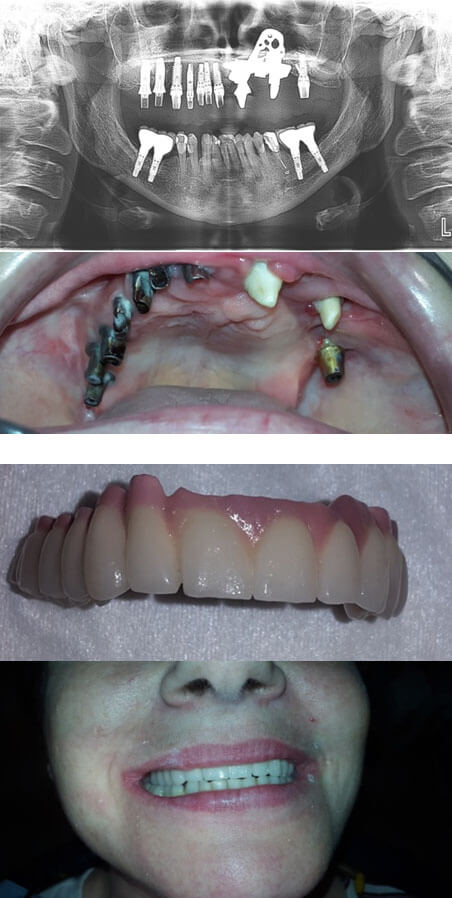

1. Персонализированный био конструкции.

2. Высокоточное производство с применением аддитивных технологий (3 D печати) из био кристалового состава, а не метала.

3. Учитывает все анатомически е особенности пациента (обходя все опасные и травматичные анатомические зоны: сосуды, нервы, пораженные участки тканей).

4. В отличии от стандартах зубных имплантатов серийного производства – не имплантат подбирают под вас, а имплантат изначально создают для вас.

5. Отсутствие необходимости выполнять сложные и травматичные реконструктивные операции Имплантата сразу можно изготовить с учетом костного или другого тканевого дефекта (может заменить сразу и костную ткань и сам зуб).

Имплантации зубов и реконструкции челюсти – Зубные имплантаты экзоскелетного типа